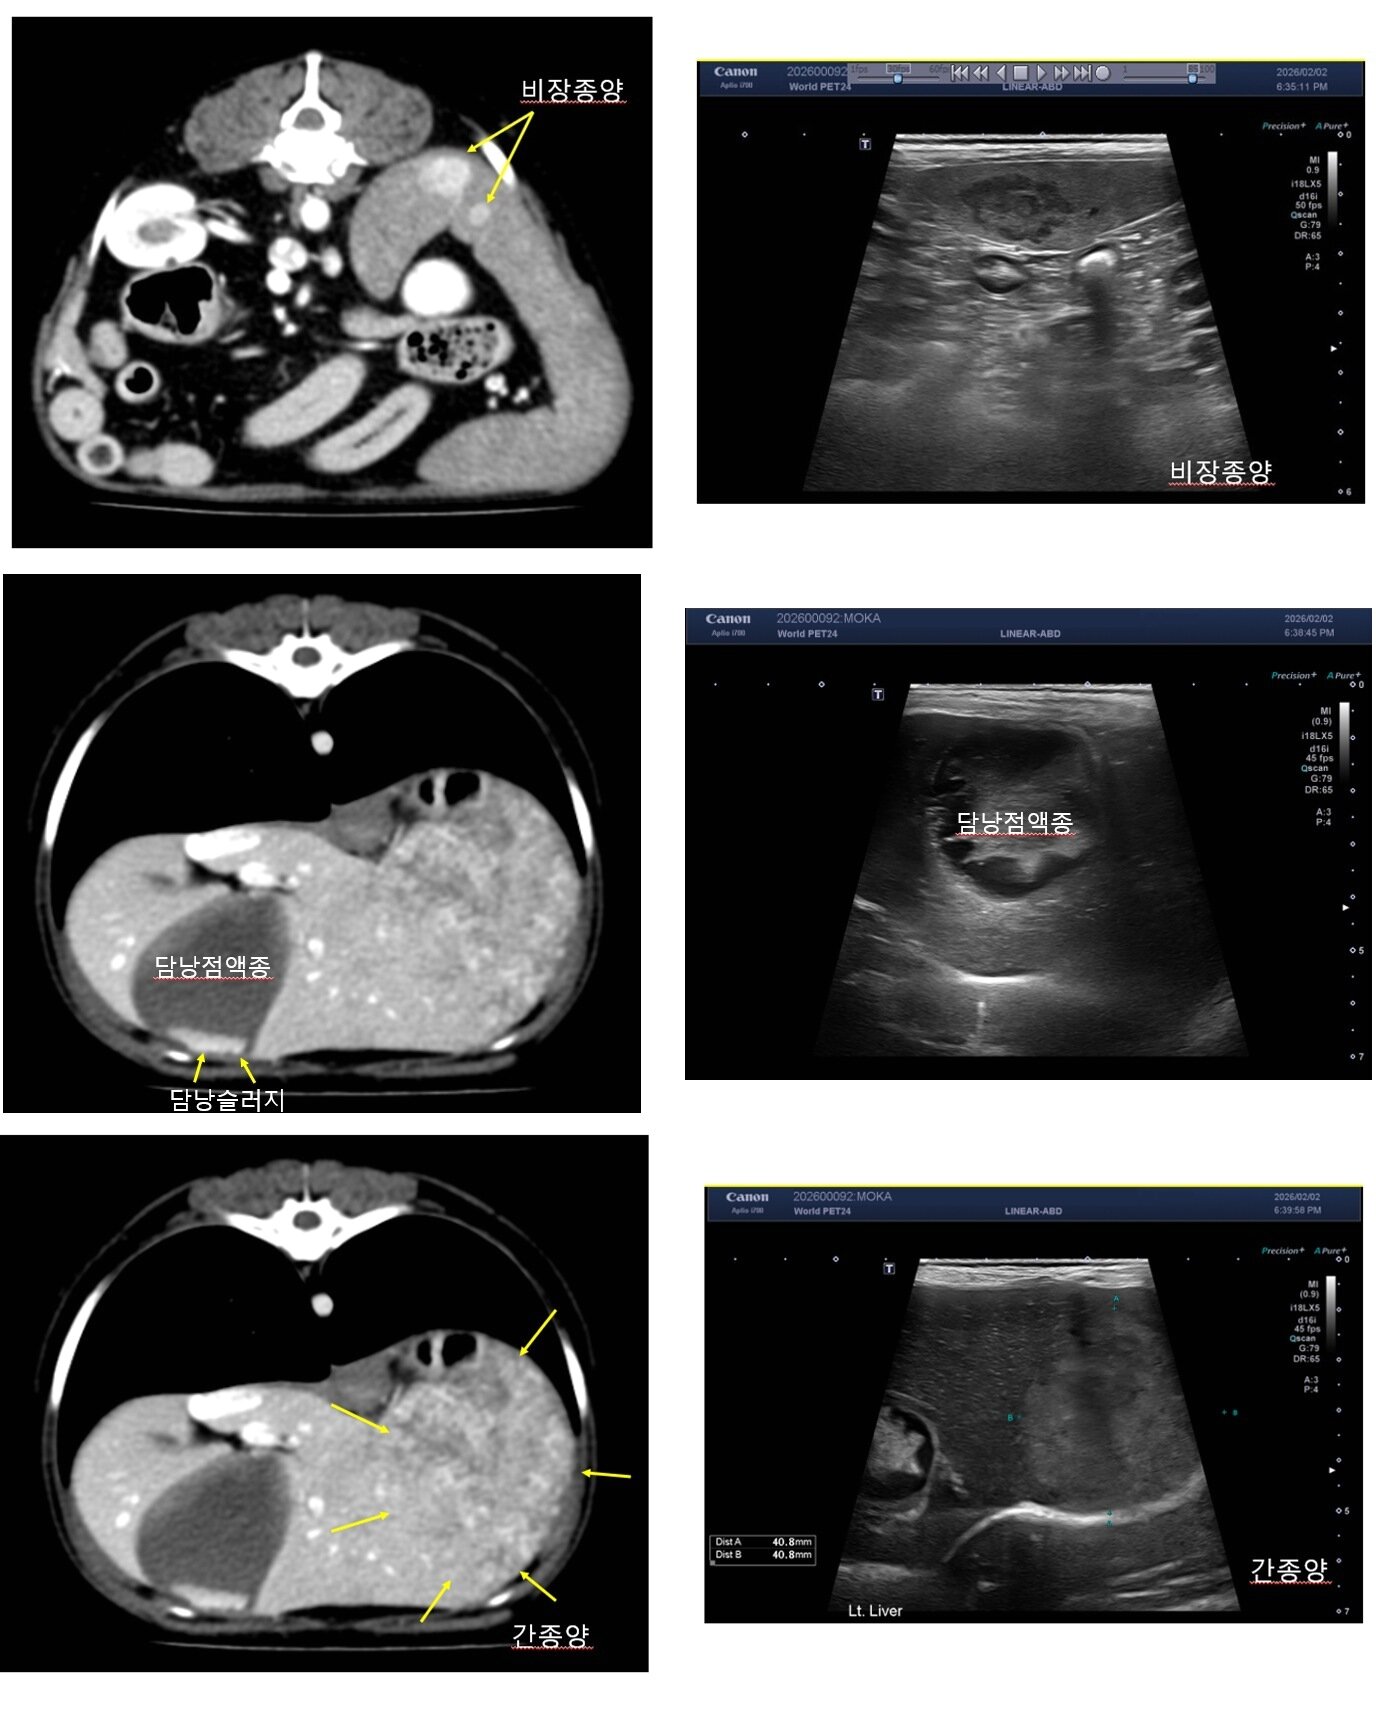

본문 이미지 - 14세 고령견에서 발견된 다발성 복강 내 장기 이상(월드펫동물메디컬센터 제공) ⓒ 뉴스1

14세 고령견에서 발견된 다발성 복강 내 장기 이상(월드펫동물메디컬센터 제공) ⓒ 뉴스1